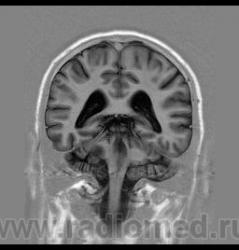

Пациент 35 лет, направлен неврологом из поликлиники с Ds: Рассеянный склероз? У данного пациента в течении года отмечается сильное головокружение и шаткость в походке, пришел на исследование на плечах у родственников. Данное исследование закачено на Dicom-сервер http: //www.radiomed.ru:8080/oviyam/oviyam? (под названием Brain-20101118).

Невринома правого слухового нерва

Если быть точным, VIII нерва;)

Более вероятнее невринома правого слухового нерва.